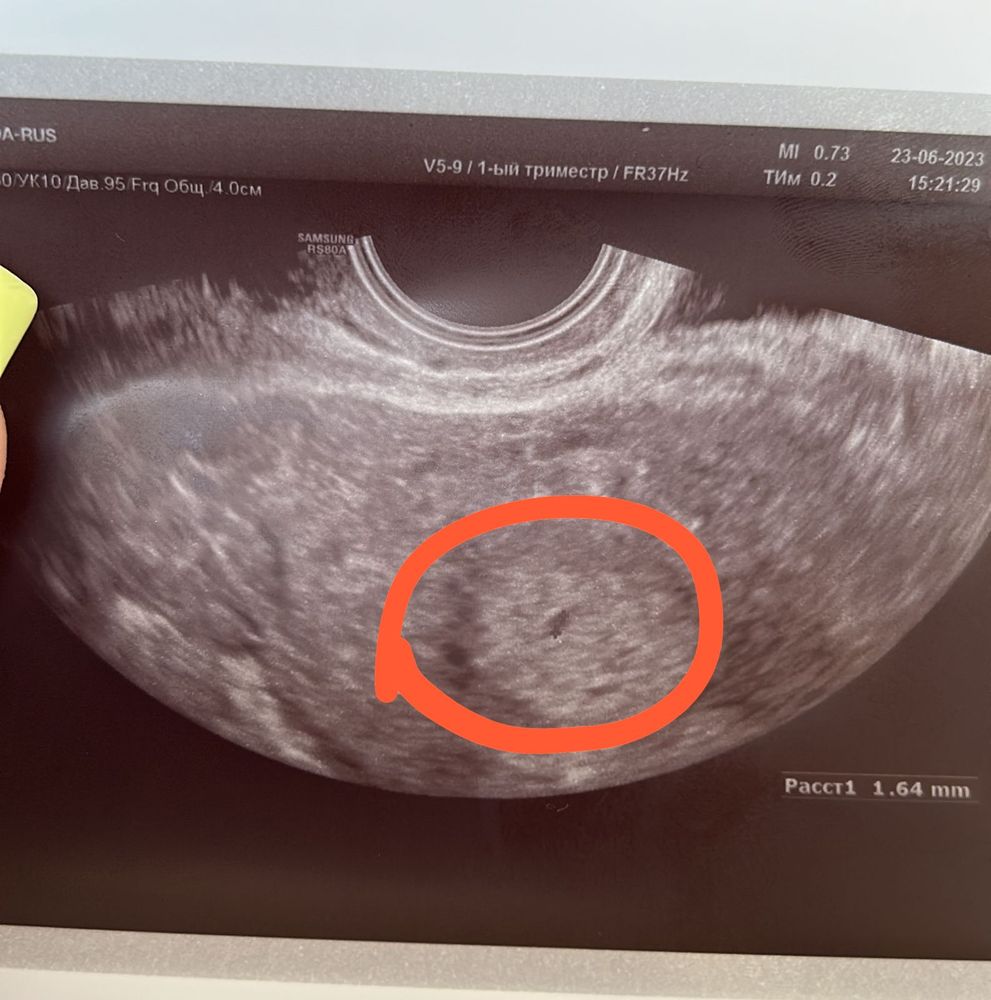

23.06 еду в другой город к гинекологам в стационар, так как боюсь, что это солидное образование в яичнике - внематочная, судя по моему поносу и самочувствию. Там мне это исключают. Якобы размер не подходит по сроку и нет кровотока. Трубы не расширены, подозрения на веематочную нет. Находят в полости матки маленькое анэхогенное зернышко 1,2мм. Фото прикрепляю. Говорят, что возможно, это и есть беременность. Я успокаиваюсь. Еду домой с назначением фолиевой и дюфастона. У меня продолжает болеть живот. Совсем не сплю ночь.